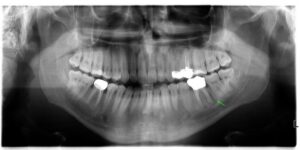

Röntgenbild eines Kiefers mit entzündeter Wurzelspitze vor einer mikrochirurgischen Wurzelspitzenresektion